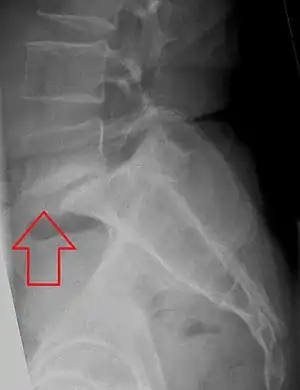

X-ray picture of a grade 1 isthmic anterolisthesis at L4-5